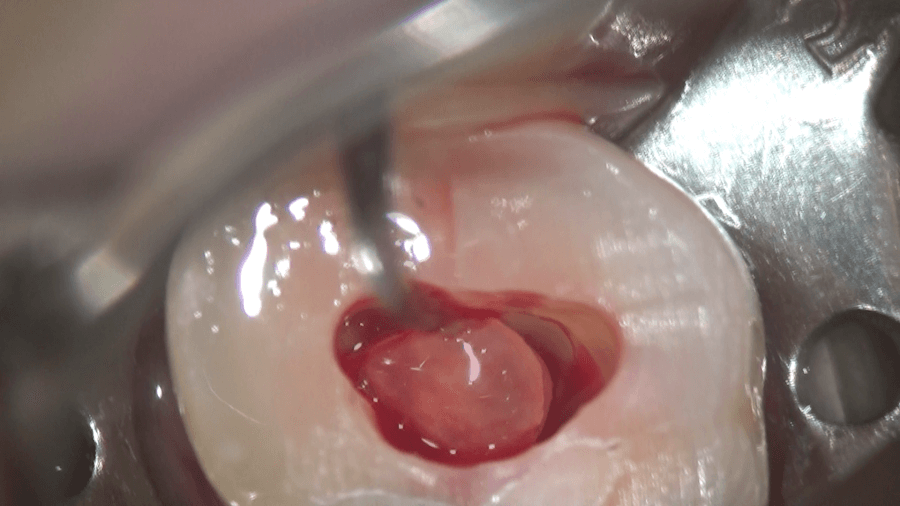

内部の軟組織である歯髄を次亜塩素酸ナトリウムで溶かします。

上部の歯髄を溶かすと、4つの根管の入り口が見えます。

超音波チップと